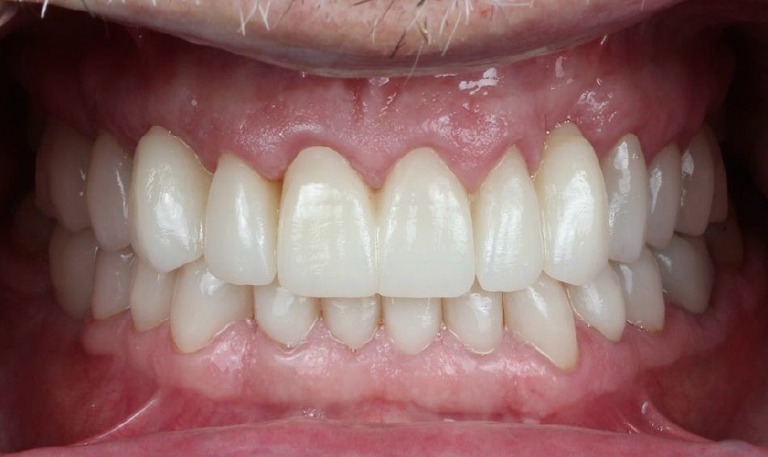

Caso de Rehabilitación completa y aumento de DV

BeforeAfter